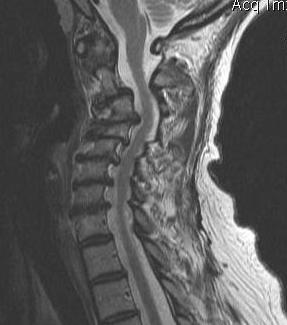

4. Evidence of cord edema / spinal cord damage

- often seen after acute injury in setting of stenosis

- best seen on STIR MRI

Spinal cord edema / injury